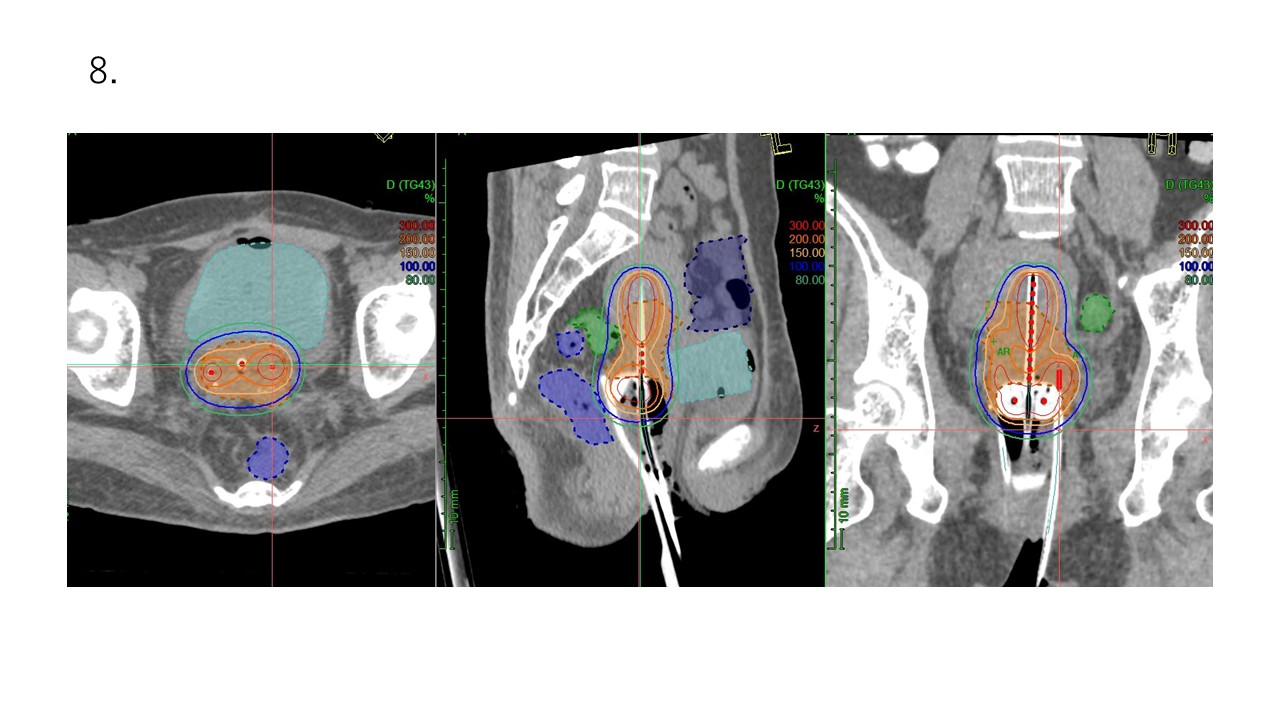

4. 3次元画像誘導小線源治療(3-dimensional image-guided brachytherapy: 3D-IGBT)

小線源治療とは、体内のがん病巣部に小さな器具(アプリケータ)を挿入し、そのアプリケータにリモートコントロールで小線源(ラジオアイソトープを封入した小さな金属カプセル)を送りこみ、体内から高線量を照射する治療です。装置(Remote After loading System)の頭文字を取って、RALS(ラルス)治療ともよばれます。

特に子宮頸癌の根治治療に不可欠の治療です。周囲の臓器(腸、膀胱など)への被ばくを最小限に抑えながら、子宮の病変部に集中した高線量の照射が可能です。

当院では同室に設置したCTを用いて高精度の3D-IGBTを行います。

アプリケータ挿入時から治療中は点滴から鎮静剤と鎮痛剤を投与し、苦痛を最小限に治療を行います。

大きな腫瘍や複雑な形状の病巣には、針状のアプリケータを追加する組織内照射併用腔内照射(ハイブリッド照射)を行います。